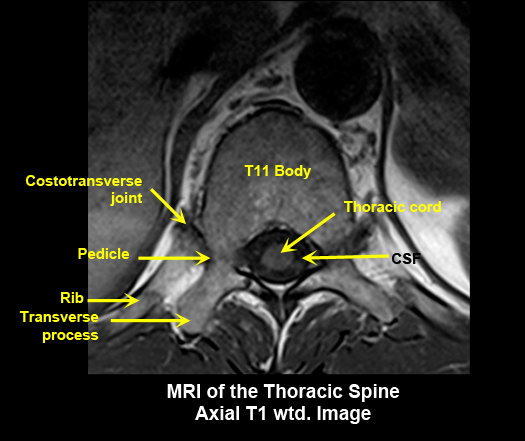

MR Brain and Spine